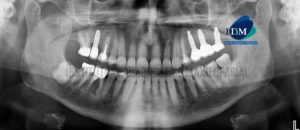

Paciente masculino de 67 años de edad, es referido al Instituto de Diagnóstico Maxilofacial (IDM) para evaluación tomográfica para planificación de implantes dentales. En la

Paciente sexo femenino de 55 años acude al Instituto de Diagnóstico por Imágenes para evaluación imagenológica previa a la confección de guía quirúrgica. A la